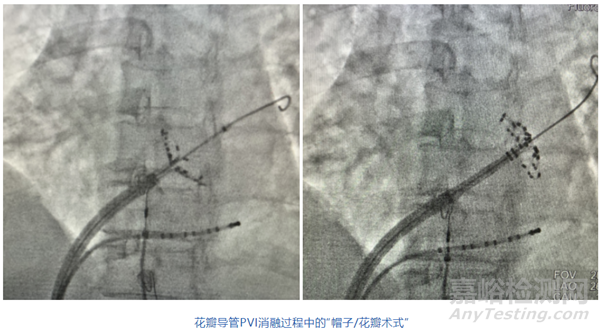

2024年10月,四川大學(xué)華西醫(yī)院曾銳教授團(tuán)隊(duì)啟動(dòng)了三維標(biāo)測(cè)系統(tǒng)指導(dǎo)下的納秒脈沖電場(chǎng)消融系統(tǒng)用于治療心房顫動(dòng)的臨床研究,并完成四例房顫患者入組。本臨床試驗(yàn)應(yīng)用了商陽(yáng)醫(yī)療研發(fā)的納秒脈沖消融系統(tǒng)(包含納秒脈沖消融儀與磁電雙定位花瓣消融導(dǎo)管),配合微創(chuàng)電生理研發(fā)的 Columbus®三維心臟電生理標(biāo)測(cè)系統(tǒng)。

在四例入組的房顫患者治療過(guò)程中,通過(guò)觀察患者體征神態(tài)、傳感器監(jiān)控肌肉顫動(dòng)等方式,確認(rèn)了患者在脈沖電場(chǎng)放電過(guò)程中無(wú)明顯肌顫及劇烈疼痛的發(fā)生。四臺(tái)手術(shù)均進(jìn)行了肺靜脈電隔離,即刻消融成功,無(wú)主要不良事件發(fā)生,患者已正常出院進(jìn)行隨訪。